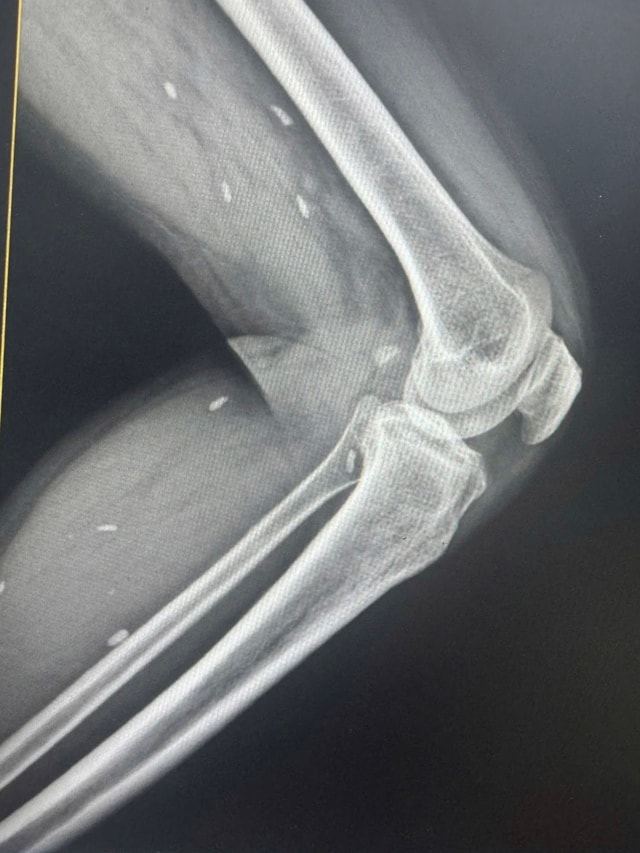

Tiến hành chụp X- quang, bác sĩ phát hiện các mô vùng xương đùi và cẳng chân bệnh nhân có nhiều kén sán kích thước như hạt gạo.

Nhiều kén sán kích thước như hạt gạo nằm rải rác ở các mô vùng xương đùi và cẳng chân bệnh nhân.

Bác sĩ Đỗ Hồng Thanh, Phó Giám đốc Trung tâm Y tế khu vực Thạch Hãn cho biết, kết quả X – quang phát hiện nhiều kén sán kích thước như hạt gạo nằm rải rác ở các mô vùng xương đùi và cẳng chân bệnh nhân.